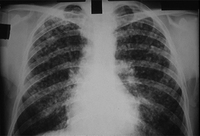

RT que muestra los cambios congruentes con silicosis simple o neumoconiosis de los trabajadores del carbón

De la colección personal de Kenneth D. Rosenman, Michigan State University